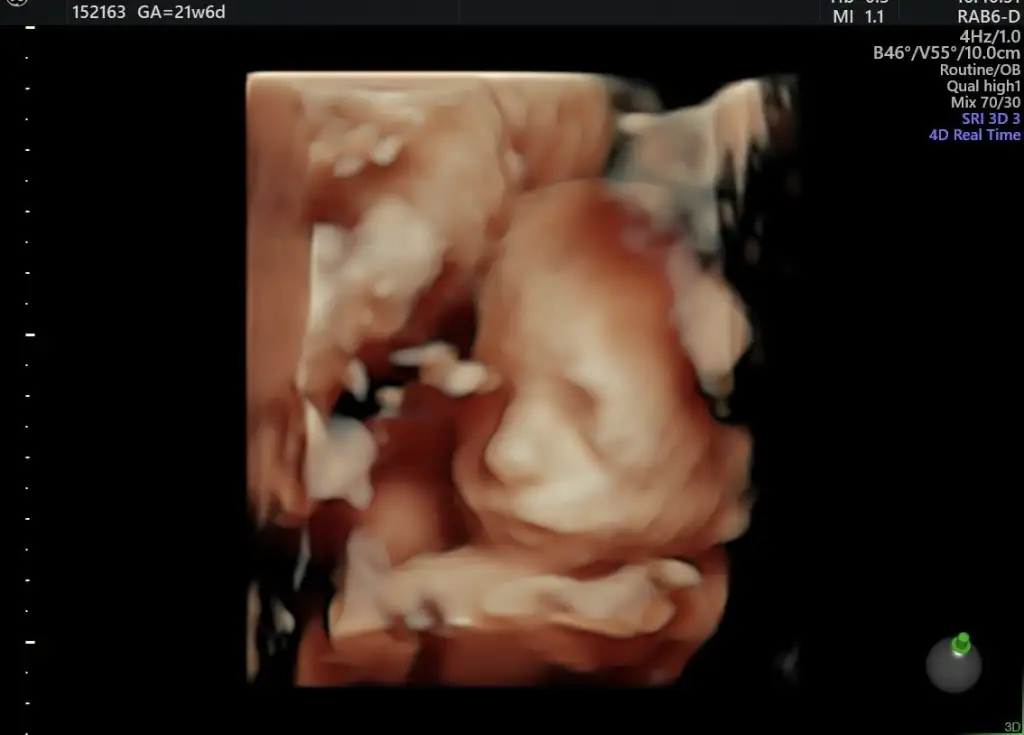

Canım şimdi şöyle başta kullandığım ilaçlar kan Grubum Eşimle akrabalıgım var mı bunları sordu. Sonra başladı ölcumleri yapmaya daha sonra ekranı döndürdü ve bana anlıyormuşım gibi anlattı tek tek beynini beyninin bölumlerını ne var ne olmazsa akıntı olur ne olması gerek ne olmaması gerektigi gibi daha sonra yüz hatları gözleri göz lenslerin burnunun ölcumunu burun deliklerini, alt dudak üst dudak yarık damak var mı yok mu baktı Cook sukur ki hepsi güzeldi daha sonra kalp kalp odacıkları damarları, kalıbın atım hızı parlaklık delik vs var mı. Hep güzeldi sonra Batın belgesi yanı karın incelemesi bagırsaklar böbrek ölcumu mide ve aklıma gelmeyen organlar. Kolları kemiklerine dek gosterdı ellerin normalliği parmakları Dhaa sonra idrar torbası var mı ona baktım mesanesine bakıldı. Cinsel organına bakıldı. Bacakları kemiklerin olcumlernjn normalliği ayaklarda ki açıya baktı şükür içe dönme vs yok parmakları saydı klasik sonra ense kaburga kemikleri ve aklıma gelmeyen daha bi cok set. Burun delikleri dahil

SATA göre 19+5 bebişim de tam çıktı normal muayenelerde önde cıkablyodu. Ama artık pozisyon gereği sureklı olcumler degsyormus. 300 gram olmuş oglusum. Boyu sormayı unttm. Ama o da ztrn Fl ölcumu ile carpımla ortalama söylüyorlar 🥰. Çok teşekkür ederimmm senin haftan tam kaç olacak canm. Bir de şöyle bir sey vardı bizde hersey grundu yani şanslıydım bide Dr gayet profesyonel belli her yerini nokta atışı gördu

Geldim kızlar oğluma bir maşallah alırım yüzünü zoraki gösterdi hep plasentanın arkasına saklanıyor ilaç verdi ateş olursa haberim olsun dedi ciğerlerime daha inmemiş 29 cm olmuş 670 grm ultrasonda da 24 haftalık çıktı çok şükür onun sağlığı yerinde 🤲🩵